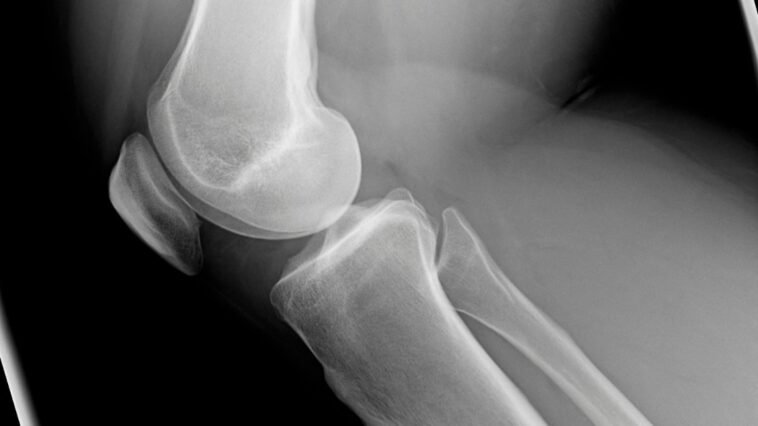

Uma das dores mais comuns relatadas em consultórios ortopédicos – a dor na frente do joelho – tem como principal causa a condromalácia patelar, que nada mais é que um amolecimento da cartilagem, ou seja, um desgaste.

Conhecida também com outros nomes como: a dor femoropatelar, a hipertensão patelofemoral, a condropatia patelar e a síndrome patelofemoral, a condromalácia patelar é consequência de uma sobrecarga mecânica na patela que, com o tempo, pode levar ao desenvolvimento de lesões na cartilagem articular e, aos poucos, a dores mais intensas.

A cartilagem que reveste a patela é uma das mais espessas do corpo, justamente para receber um excesso de força que habitualmente passa pela articulação. Quando a musculatura está fraca e o alinhamento da perna é perdido, porém, a força que o corpo dispende sobre a patela é muito maior. Se isso não for devidamente corrigido, poderão ocorrer lesões da cartilagem da patela.

Enquanto as lesões ainda são superficiais, a estrutura óssea não contribui para as dores, porém, ao atingir camadas mais profundas, a proteção oferecida pela cartilagem vai sendo perdida ao longo do tempo, piorando a dor e, possivelmente, contribuindo para o desenvolvimento de uma artrose no joelho.